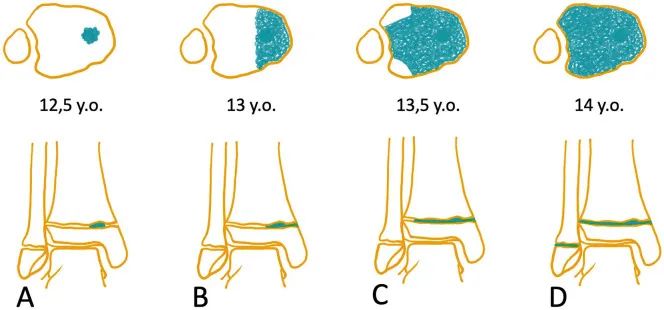

关节镜辅助下复位固定。A(踝关节镜前内侧入路)见到骨折部位移位,影响关节匹配性。B(踝关节镜前内侧入路)使用探钩复位骨折块。C(踝关节镜前外侧入路)确认骨折块复位。D(踝关节镜前外侧入路)在关节镜监视下经皮打入克氏针。图源:DOI: 10.1007/s00167-006-0234-3.